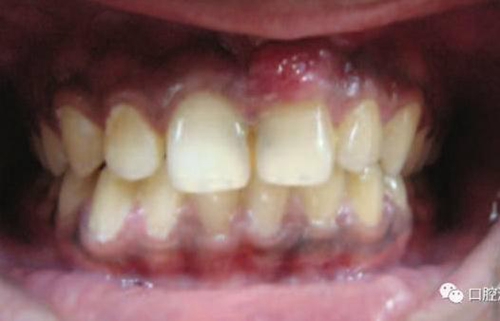

11、21 治療前

對瘺管位置進行激光氣化